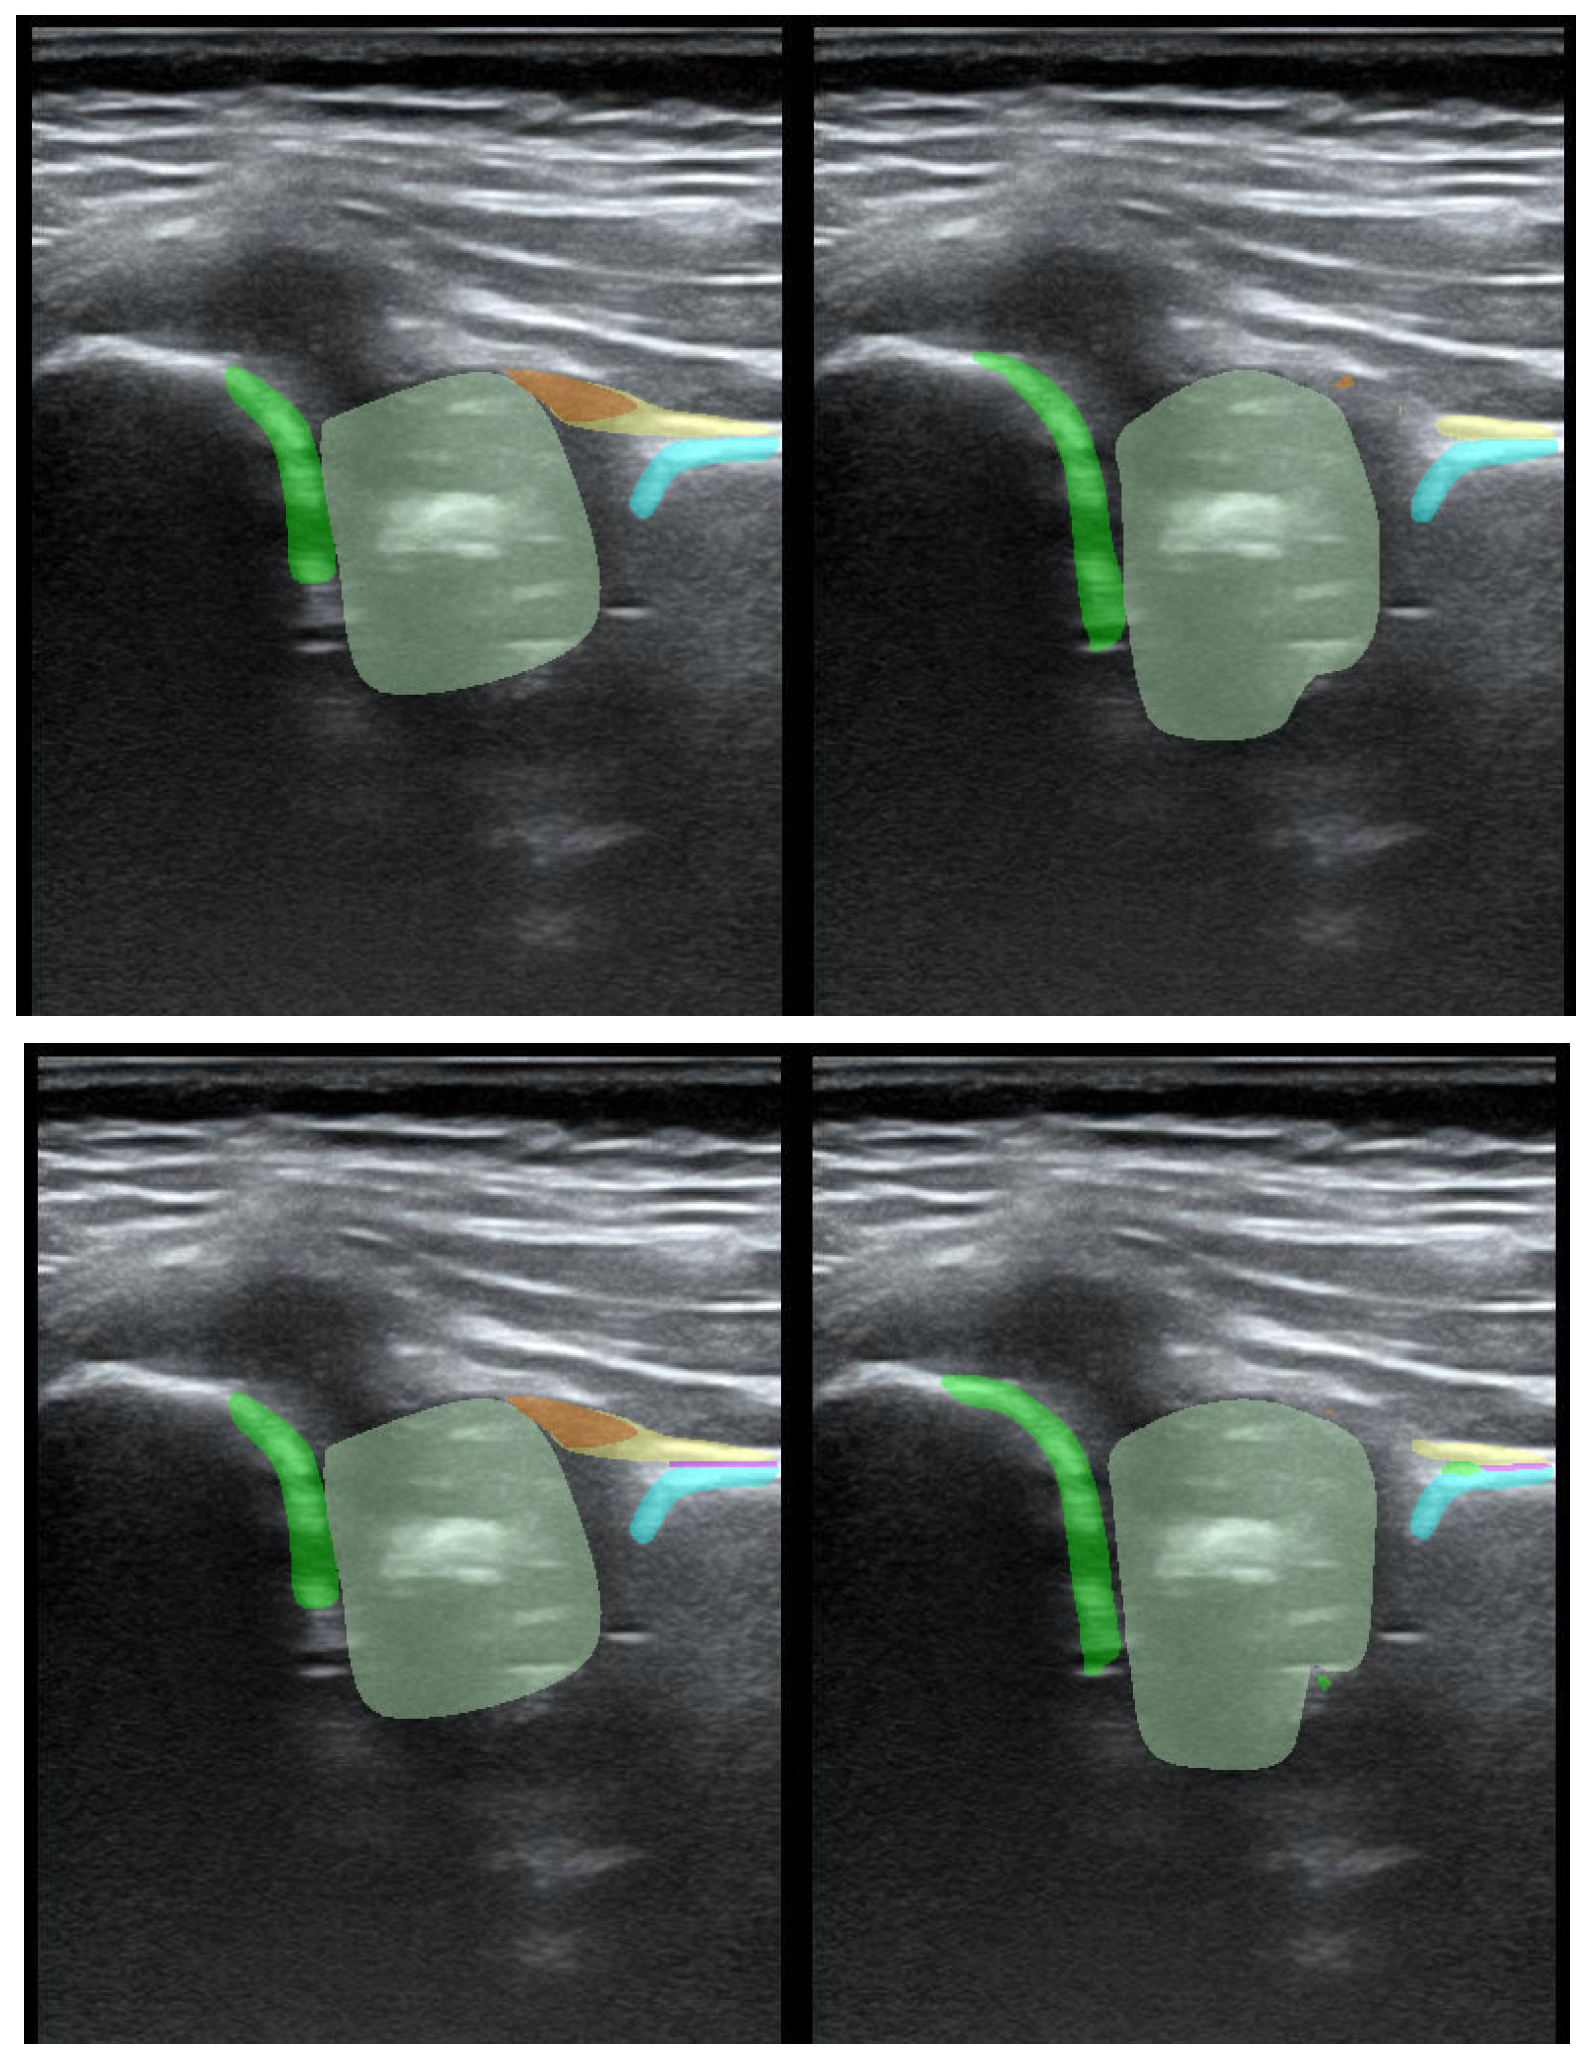

To illustrate the performance of the segmentation model, a comparison is presented between the labels obtained by the segmentation model and the ground truth labels. Two models were analyzed: Model-8 (generating segments for eight classes) and Model-5 (generating segments for five classes). Both the cases with the highest quality model labels and the cases where the model labels were less accurate are presented. Figure 3 shows one of the best cases, in which Model-5 and Model-8 accurately labeled the classes relative to the doctor’s labels. The worst-case scenario was also analyzed, in which the prediction results differ significantly from the ground truth labels (Figure 4).

Figure 3. High-quality model labels (upper—Model-8) and (lower—Model-5). Annotated mask on the left, model mask on the right.

Jcm 14 06332 g003

Figure 4. Low-quality model labels (upper—Model-8) and (lower—Model-5). Annotated mask on the left, model mask on the right.